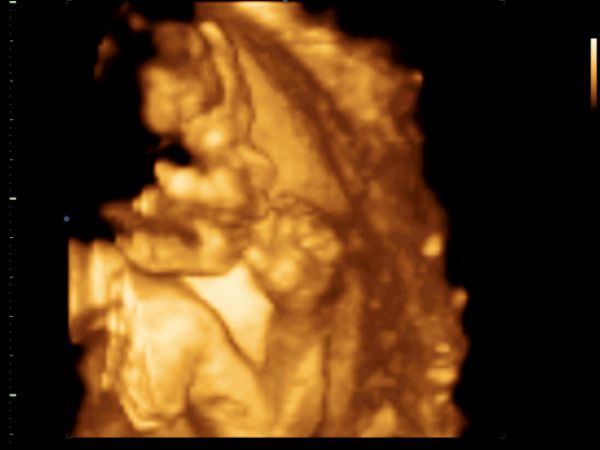

Ahojte holky, tak dneska kontrola ultz dopadla výborně, vše je v pořádku, 18+3 týden, váží 240 gm a je to :°~°: , takže tatka je nadmíru spokojen a nadšený, že má pokračovatele rodu.